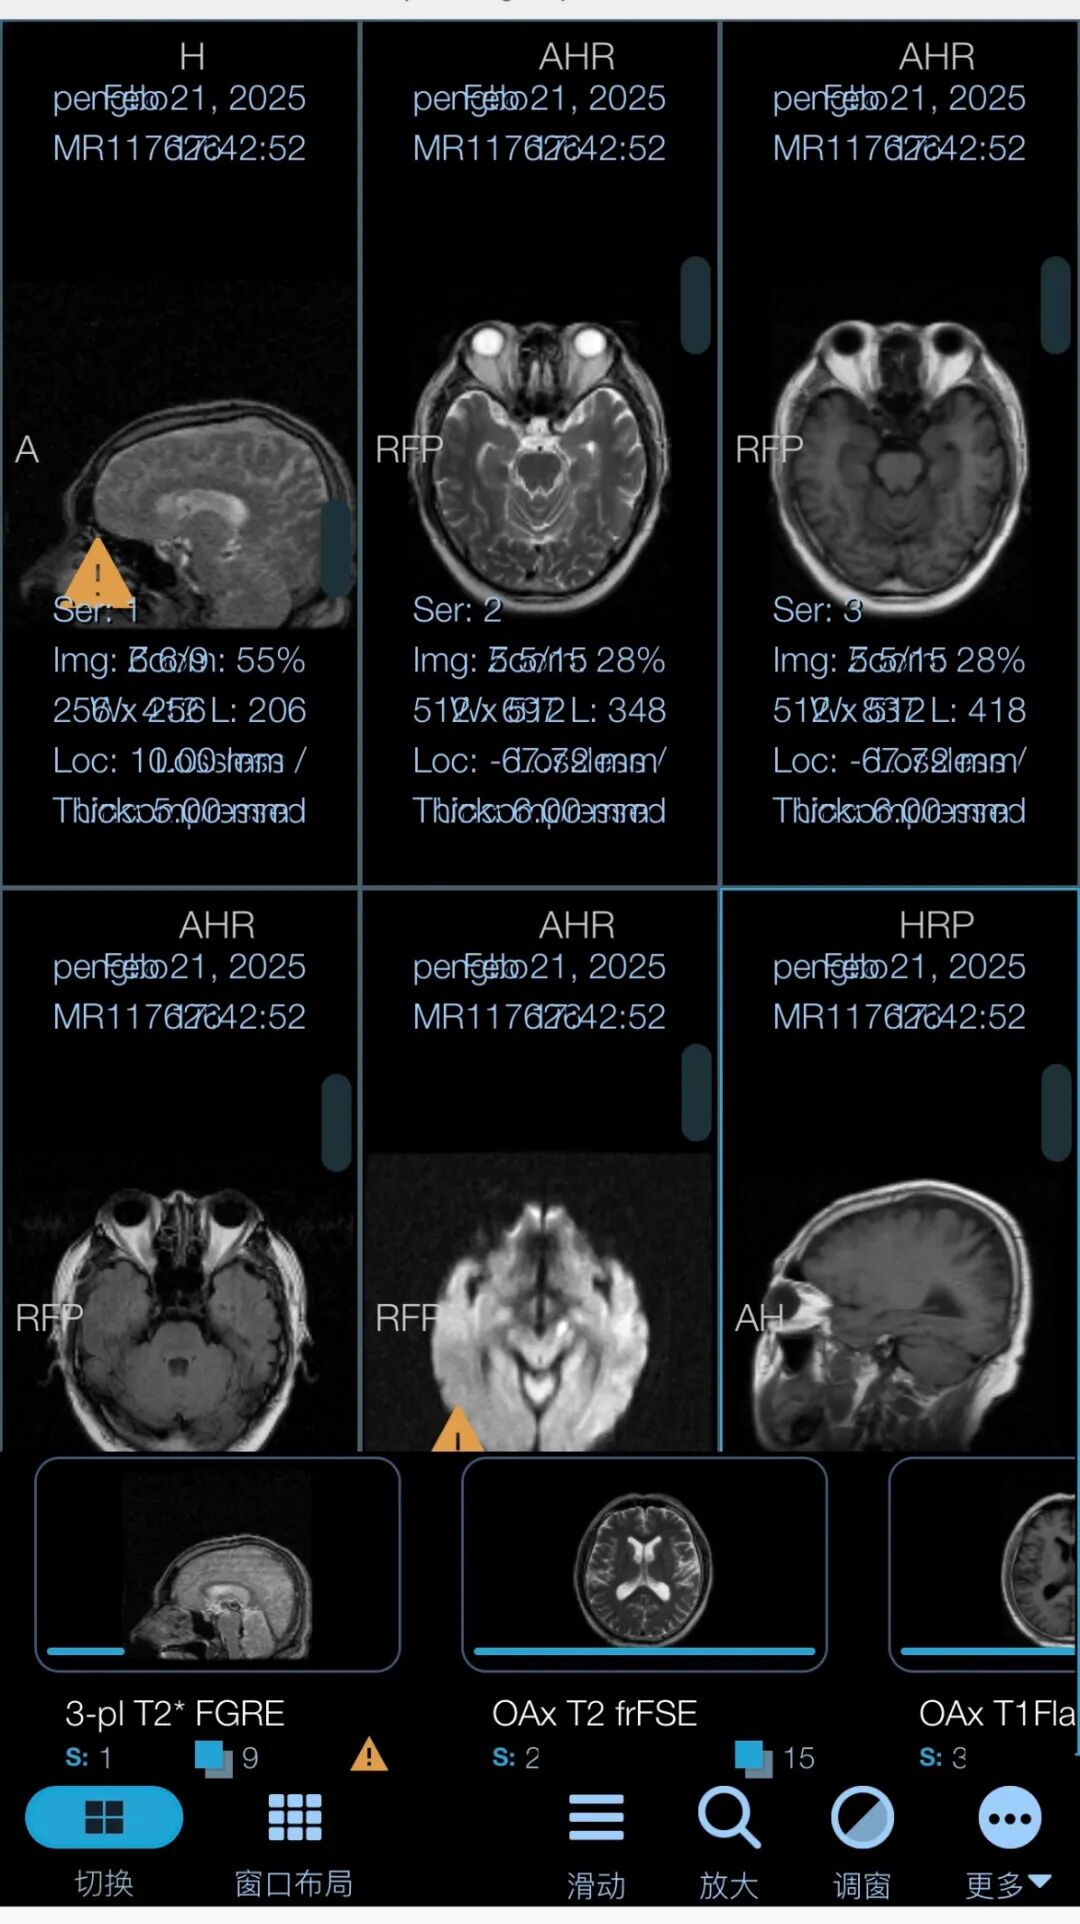

第三步:点击“序列胶片”查看原始胶片记录。

第四步:点击“切换”可查看多张胶片信息,本胶片信息可反复查看,易于长期保存,长按也可保存至手机相册。